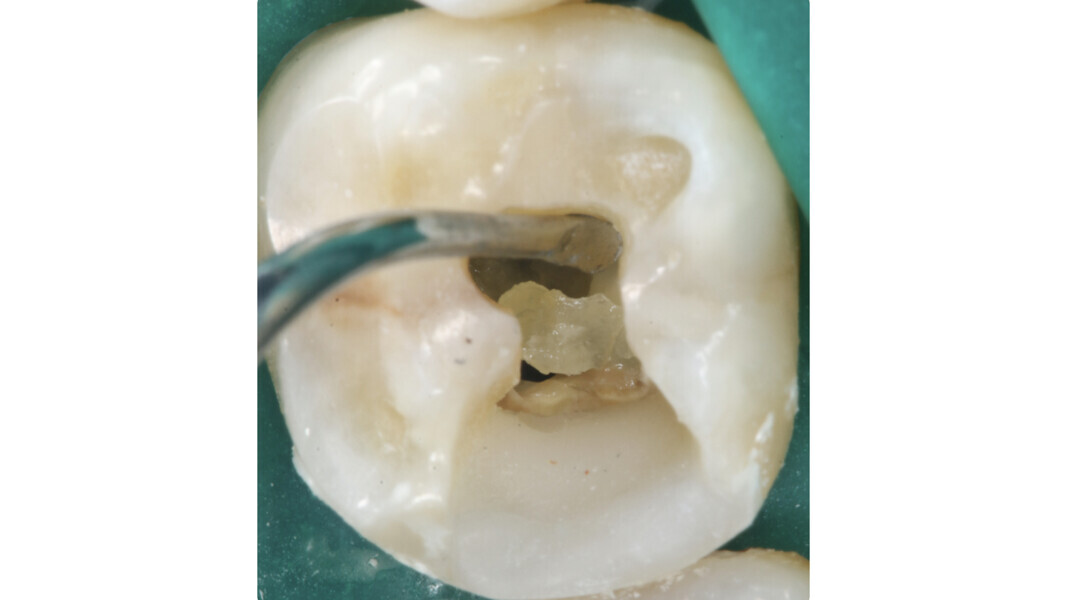

La première étape est stratégique et préparatoire à la réalisation des étapes suivantes. Tout d’abord, la forme doit permettre une visibilité totale du plancher de la cavité pulpaire et des orifices canalaires. L’élimination incomplète du plafond de la cavité pulpaire ou d’une partie du tissu pulpaire (par exemple, les cornes pulpaires) peut compromettre la réussite du traitement.

- Loi du changement de couleur : la couleur du plancher de la cavité pulpaire est toujours plus sombre que celle des parois qui lui sont adjacentes.

- Loi de localisation des orifices n° 1 : les orifices des canaux radiculaires sont toujours localisés à la jonction des parois et du plancher de la cavité pulpaire.

- Loi de localisation des orifices n° 2 : les orifices des canaux radiculaires sont localisés dans les angles de la jonction des parois et du plancher de la cavité pulpaire.

- Loi de localisation des orifices n° 3 : les orifices des canaux radiculaires sont localisés à l’extrémité des lignes de fusion développementales de la racine.